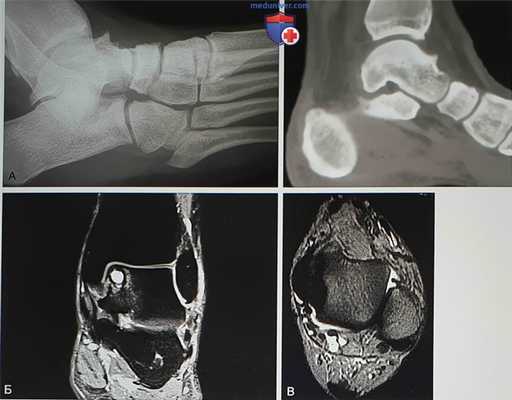

- На рентгенограммах с нагрузкой в боковой проекции могут быть видны остеофиты большеберцовой и таранной костей. В переднем завороте могут быть свободные суставные тела, могут быть признаки перелома остеофитов (рис. 1, А):

• Магнитно-резонансная томография (МРТ) позволяет увидеть выпот в переднем отделе голеностопного сустава, синовит, а также остеофиты (рис. 1, Б). Может быть видна гипертрофированная связка Бассетта (рис. 1, В)

• В голеностопном суставе могут определяться остеохондральные кисты и хондральные повреждения, свидетельствующие о более выраженных изменениях, ухудшающих долговременный прогноз

- Компьютерная томография позволяет оценить размеры и локализацию остеофитов, что может оказывать влияние на выбор артроскопических портов. Также КТ позволит увидеть субхондральные кисты и участки склероза в голеностопном, а также в смежных суставах